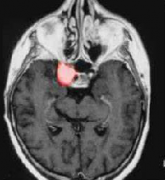

脑膜瘤

枕骨大孔区脑膜瘤手术成功率高吗?

枕骨大孔脑膜瘤(FMM)继续挑战神经外科医生,因为这些病变与不能牺牲或缩回的神经和血管结构密切接触。尽管显微外科手术和颅底外科手术有了很大的发展,但FMM的治疗仍然引起了关...